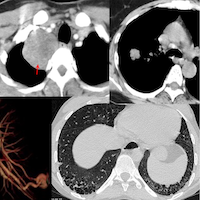

31-yrs old with scleroderma and known scleroderma ILD unchanged for 1 year.

The video describes the case and the 3 different patterns noted - a fibrotic NSIP pattern, a non-fibrotic BIP pattern and DPO, suggesting underlying CiOP - hence a mixed NSIP/BIP/OP pattern.